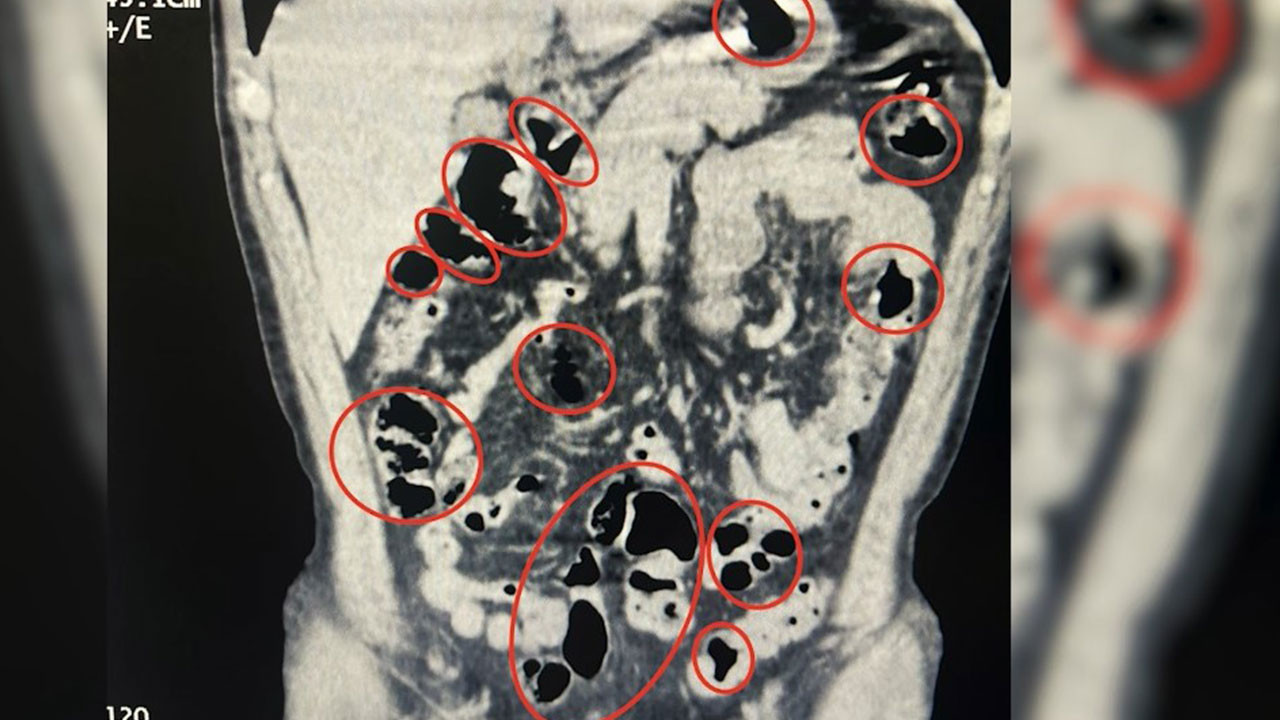

Bitlis'te üzerlerinde yapılan aramada ve mide ile bağırsaklarında toplam 50 kapsül halinde 385 gram metamfetamin ele geçirilen 2 şüpheli gözaltına alındı.